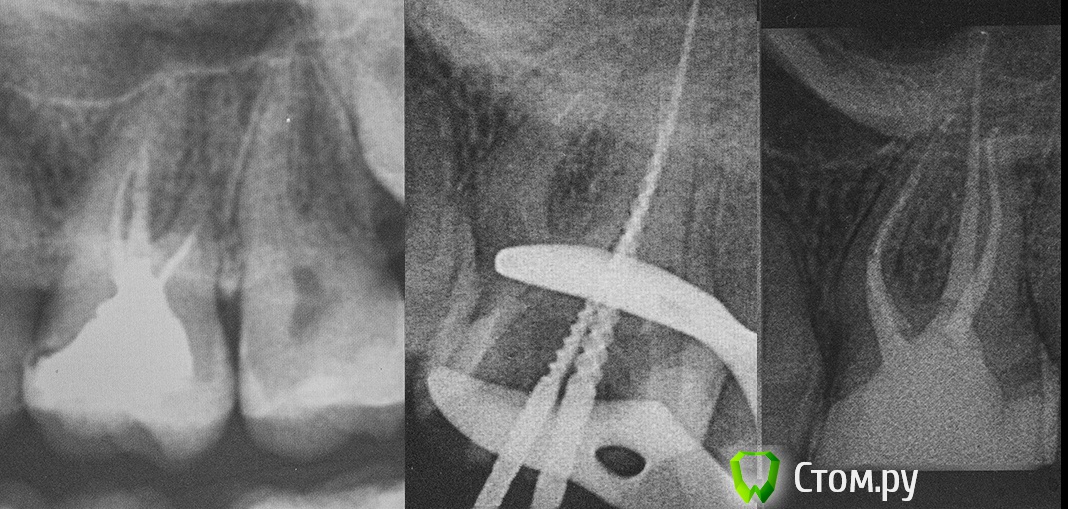

M@estro Опубликовано 6 октября, 2014 Автор Поделиться Опубликовано 6 октября, 2014 Пролог : http://s008.radikal.ru/i303/1410/73/eb9f197b9a6c.jpg В этот момент я подумал - "удалять". И 30 минут твердил пациенту именно это. 1 Ссылка на комментарий

M@estro Опубликовано 6 октября, 2014 Автор Поделиться Опубликовано 6 октября, 2014 (изменено) Только не говори что ты полечил это? Да,я полечил ) Уж пару месяцев назад, только руки дошли оформить)) а дальше, что дальше то?) А дальше всё довольно прилично )) В этом кейсе меня буквально спас супермат ( круговая затягивающаяся матрица от керр) . Естественно, фотографировать конструкцию не было желания , потому как мы спешили ) Встала матрица на удивление плотно - и позволила восстановить дистальную стенку. Остальное - дело техники. ММ чёткий , соединяется с МБ . Всё отмыто и запаковано ( честно - уже не помню ,чем паковал, но , вероятно,что дистальный сквирт, МБ + МЯ - comb. comp. + сквирт мм. расширял до 35 /04 ( дистальный - 50) . http://s019.radikal.ru/i618/1410/eb/e8417931d975.jpg P.s. Был пульпит под штамповкой. Я про себя ругался чёрными словами - но всё получилось, несмотря на устрашающие фотки ) Ноенко - стайл Изменено 6 октября, 2014 пользователем M@estro 5 Ссылка на комментарий